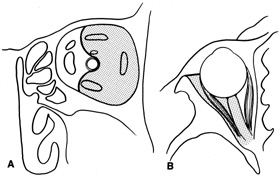

The other important consideration in planning orbitotomy is the position of the tumor within the orbit. Lesions generally may be categorized as either anterior (superficial) or posterior (deep). They can be further categorized by their relationship to the optic nerve (medial, lateral, superior, or inferior to the optic nerve). It may be helpful to further classify the location of lesions relative to adjacent anatomic structures in the orbit. Many surgeons prefer to conceptualize orbital pathologic processes as being located within one or more of seven “surgical spaces” within or around the orbit (Fig. 5). These spaces include:

Fig. 5. Axial drawing of anatomic spaces of the orbit. (1, intraconal space; 2, extraocular muscles; 3, peripheral surgical space; 4, subperiosteal space; 5, preaponeurotic space; 6, Tenon's space; 7, periorbital tissues.)

1. Central surgical space (intraconal space)

2. Extraocular muscles

3. Peripheral surgical space (extraconal space)

4. Subperiosteal space

5. Preaponeurotic space

6. Tenon's space

7. Periorbital tissues

The central surgical space is bounded by the intermuscular septum, which connects the four rectus muscles in the coronal plane. This space also is described as the retrobulbar or intraconal space, and it contains the optic nerve, intraconal fat, and various vascular and neural structures. Primary orbital tumors such as cavernous hemangiomas or optic nerve meningiomas originate in the central surgical space.

Many orbital processes involve the extraocular muscles, primarily or secondarily, making it useful to classify the extraocular muscles as residing in their own separate surgical “space.” Conditions affecting the extraocular muscles include thyroid orbitopathy, myositis, and a variety of neoplastic conditions.

The peripheral surgical space, also known as the extraconal space, lies outside the intermuscular septum but within the periorbita. This space contains a scant amount of orbital fat, the superior oblique muscle and trochlea, inferior oblique muscle, and lacrimal gland. Other important nerves and vessels extend into the space, such as the superior ophthalmic vein. A variety of pathologic processes may encroach on the peripheral surgical space.

The subperiosteal space is a potential space lying between the orbital bones and periorbita. The periorbita may provide a barrier to extension of neoplastic and infectious processes originating in the adjacent sinuses or intracranial cavity. Frequently, the subperiosteal space may fill with blood after orbital fracture or infection when associated with a paranasal sinusitis.

The preaponeurotic space is actually an anterior extension of the extraconal space. Because this space is superficial and readily accessible, sometimes it is referred to as its own orbital compartment. Frequently, neoplasms affecting the lacrimal gland, such as lymphoma, extend forward into the preaponeurotic space.

Tenon's space is a potential space between the sclera and Tenon's capsule. Tumors originating in the eye, such as choroidal melanoma, may extend into Tenon's space.

Secondary orbital tumors may arise from periorbital tissues and secondarily invade the orbit. Cutaneous malignancies arising in the eyelid or facial skin may extend posteriorly through the orbital septum, whereas nasal and paranasal sinus tumors may grow through the orbital bones into or through the subperiosteal space. Tumors arising within the cranial cavity, such as sphenoid wing meningiomas, also may affect the orbit secondarily.